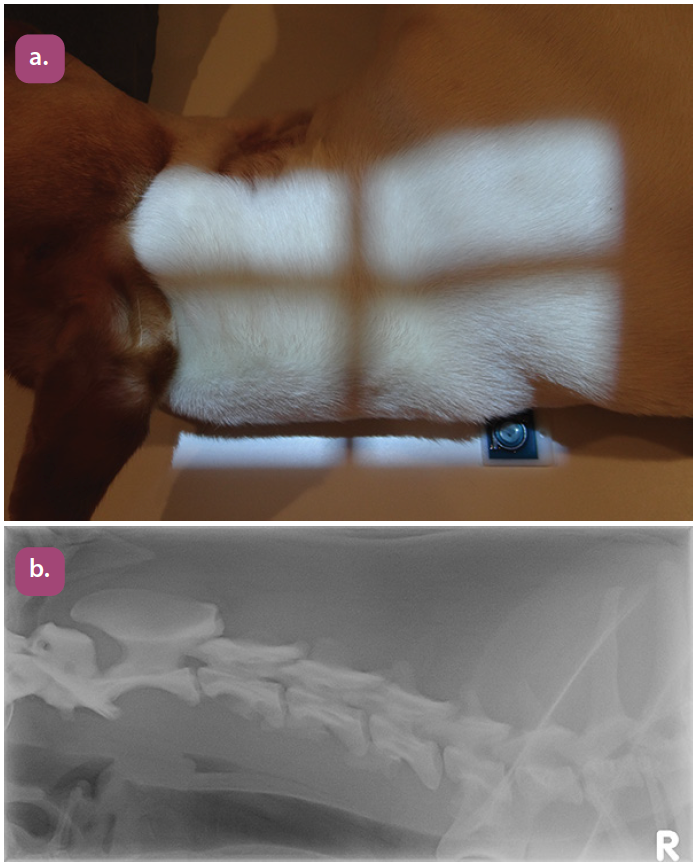

lateral cervical spine extended projection